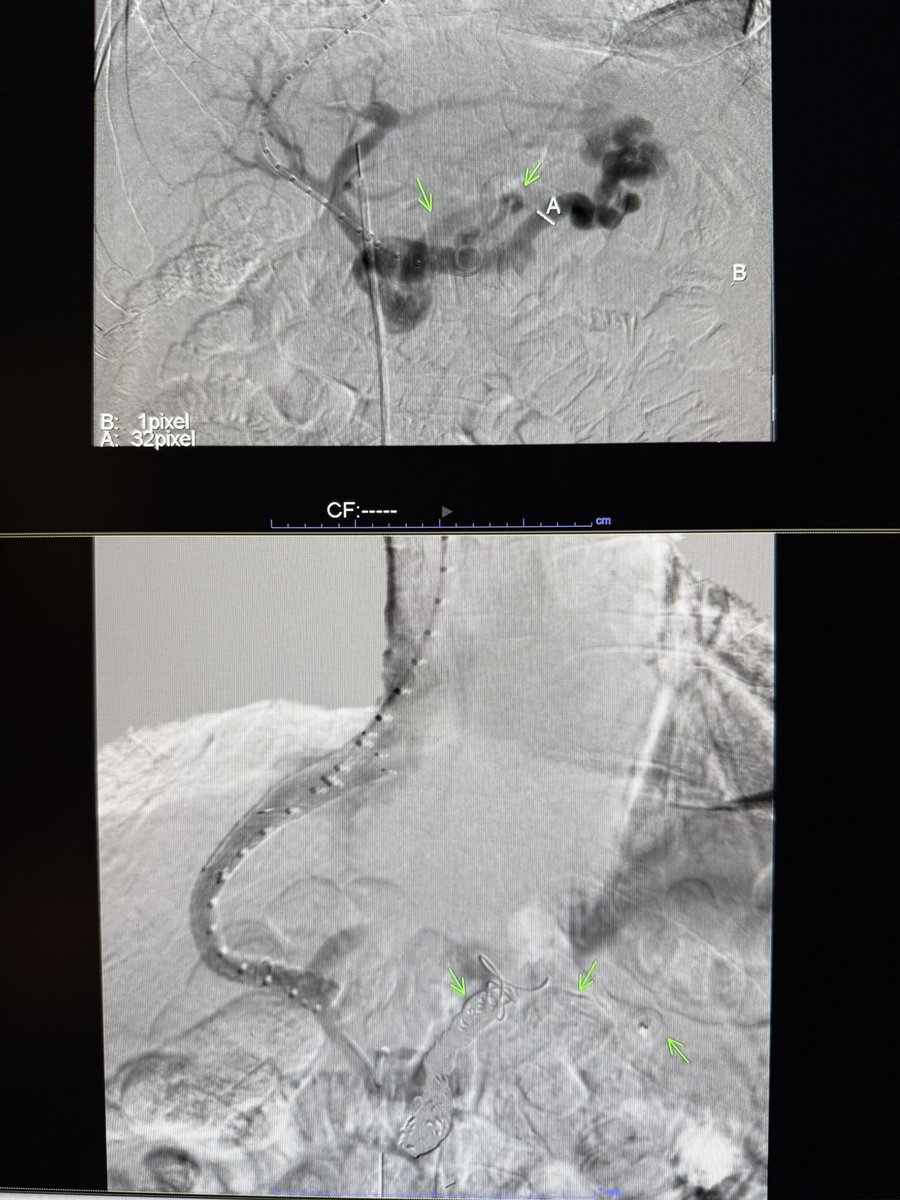

#CTO of Nephroureteral stents! Can’t cross with any wire on shelf! What’s your rec to help out your junior colleague to swap them ? May be your trick can come handy & help @SIRRFS one day ! @kmadass I know it ain’t arterial 😁 @keithppereira @SDhandMD @IRKhalsa @IR_Doctor

@t_intheleadcoat @SIRRFS @kmadass @keithppereira @SDhandMD @IRKhalsa @IR_Doctor Encrusted? These can go sideways fast if not careful. Often a glidewire can track alongside the stent (similar to clogged antegrade PCN/GJ tubes). 👀 to see what you did

@t_intheleadcoat @SIRRFS @kmadass @keithppereira @SDhandMD @IRKhalsa @IR_Doctor These are tough cases for a routine exchange- and go by many names- reverse PCN- diversionary catheter- and "single J"- if no wire will go through, can always take a KMP alongside it, get a wire up and slowly pull as to not dislodge your buddy wire, otherwise, crossing catheter